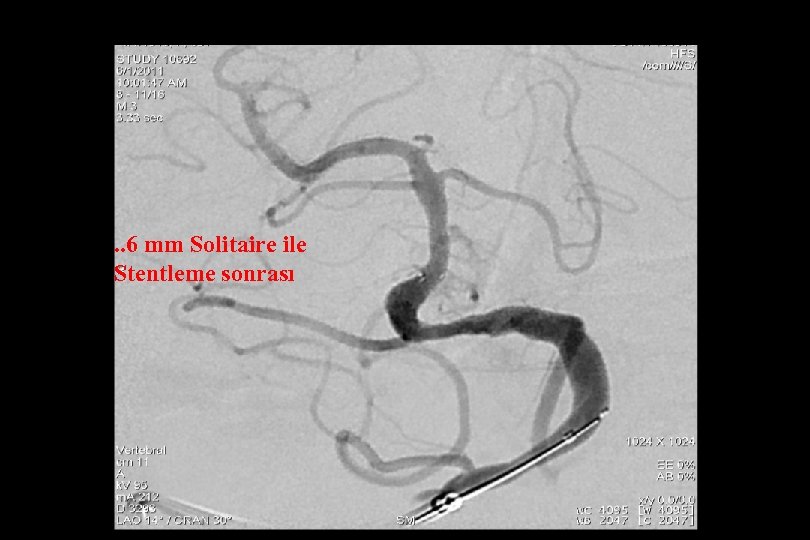

. . 6 mm Solitaire ile Stentleme sonrası

66 mm Solitaire ile post stent

Post stent